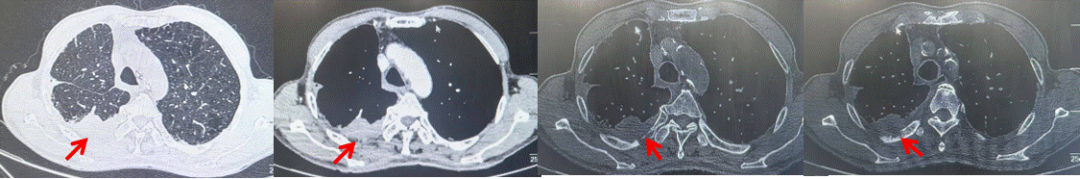

2024.11.19患者出现右侧胸痛,复查胸部CT检查示右侧胸膜肿物,大小约31mmX24mm,右侧4、5肋骨骨质破坏,考虑转移(如图2)。建议患者穿刺活检取病理明确诊断,患者拒绝,经MDT会诊后结合影像学表现及病史考虑为胸膜转移,肋骨转移,分期为rT0N0M1a IVA期,DFS仅仅17个月。2024.12.05起行信迪利单抗联合培美曲塞+卡铂方案治疗4周期,复查胸CT评效PR(如图3)。之后给予信迪利单抗+培美曲塞维持治疗6周期,期间复查CT评效PR(如图3)。目前信迪利单抗+培美曲塞维持治疗中,截止至目前PFS约为8个月,治疗期间未出现明显毒副反应。

图3:患者免疫联合化疗治疗后胸部CT,(A、B)图展示信迪利单抗联合培美曲塞+卡铂治疗

4周期(2025.02)疗效,(C、D)图展示信迪利单抗+培美曲塞维持治疗6周期(2025.07)疗效